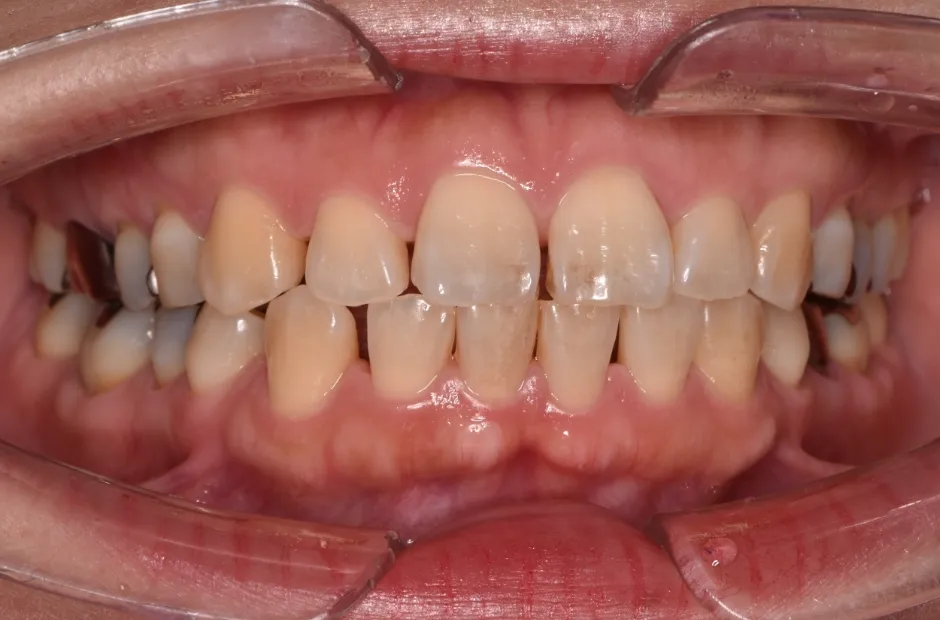

叢生

| 診断名・主訴 | 叢生 |

|---|---|

| 年齢・性別 | 43歳・女性 |

| 治療期間・回数 | 2年7か月 27回 |

| 治療に用いた主な装置 | 舌側矯正 |

| 抜歯部位 | 両顎4,4 |

| 治療費 | 100万円(税抜) |

| リスク・副作用 | 装置による違和感・疼痛・歯肉退縮・歯根吸収・虫歯のリスクなど |

治療前